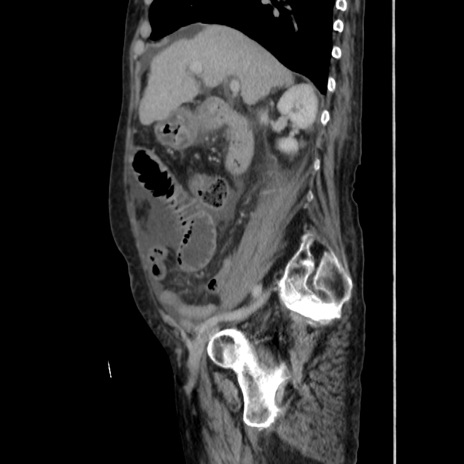

症例31(矢状断像)

【症例】80歳代 女性

【主訴】腹部膨満感

【現病歴】他院にて肝硬変にてフォロー中。1週間前から便秘、腹部膨満感、臍部腫瘤あり受診となる。

【既往歴】肝硬変

【身体所見】腹部膨隆あり、皮膚変化なし、疼痛なし。

【データ】WBC 4600、CRP 0.25